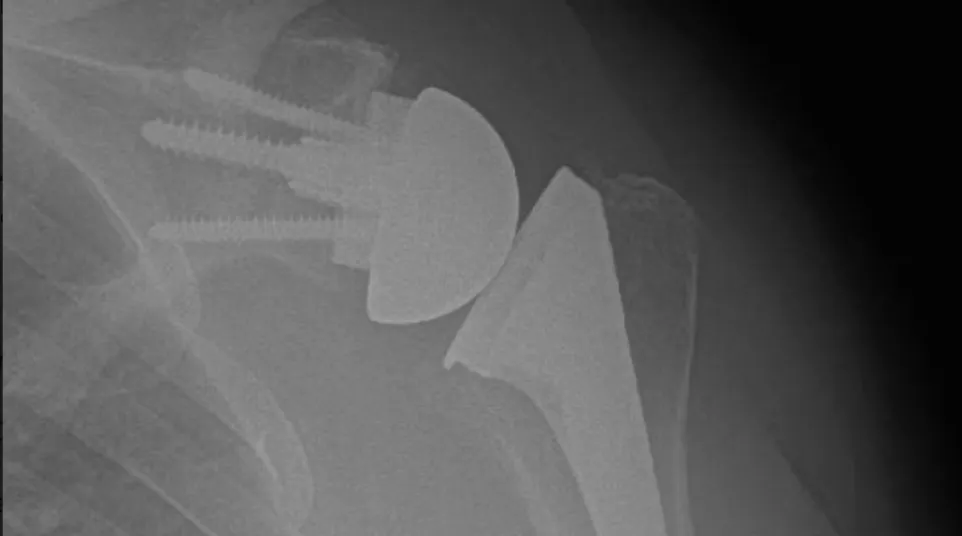

X-ray showing shoulder joint replacement with metal prosthesis and screws in humerus bone.

Reverse Shoulder Replacement:

This innovative technique is primarily used for patients with a torn rotator cuff and severe arthritis, fractures, irreparable chronic rotator cuff tears or those who have had previous unsuccessful shoulder replacement surgeries (revision shoulder replacement). Some patients who have normal rotator cuffs with severe arthritis can benefit from a reverse shoulder replacement if they are older or have worn away too much bone on the socket. In reverse shoulder replacement, the normal ball-and-socket structure is reversed; the ball component is attached to the shoulder blade, and the socket is placed at the top of the humerus. This arrangement allows the deltoid muscle to power the arm, compensating for the damaged rotator cuff or alterations in anatomy.